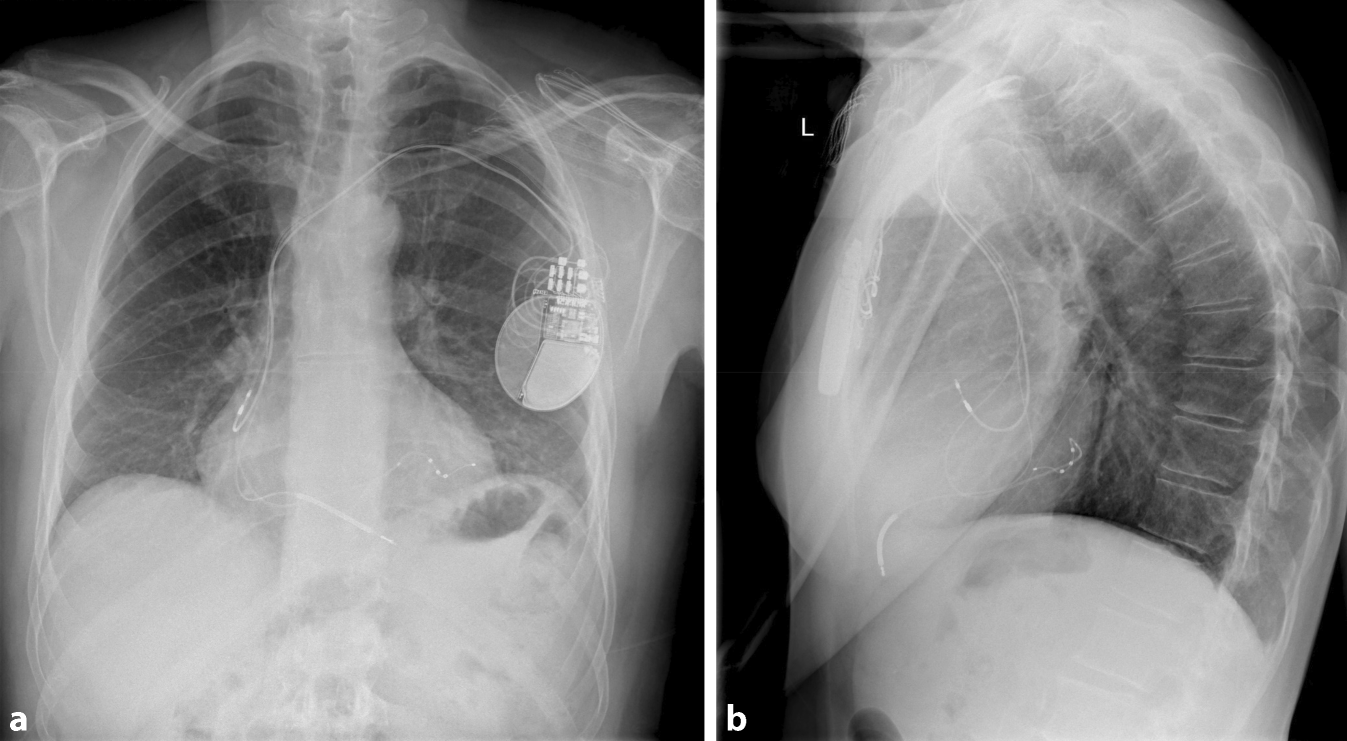

CRT verbessert die Herzfunktion, indem sie die ventrikuläre Kontraktion bei Patienten mit Herzinsuffizienz synchronisiert, insbesondere bei Patienten mit Linksschenkelblock (LBBB) oder anderen Formen elektrischer Dyssynchronie. Das CRT-Gerät umfasst typischerweise 3 Elektroden: eine im rechten Vorhof (RA), eine im rechten Ventrikel (RV) und eine im Koronarsinus zur Stimulation der lateralen Wand des linken Ventrikels (Abb. 1). Bei Patienten mit permanentem Vorhofflimmern (AF) kann auf die Vorhofelektrode verzichtet werden, und der entsprechende Anschluss am Gerät kann blind verschlossen werden.

Abb. 1

a Röntgenaufnahme des Thorax in p.-a., welches die 3 Elektroden eines CRT-Schrittmachers in loco typico zeigt. b Laterale-Thorax-Rröntgenaufnahme; die 3 Elektroden eines CRT-Schrittmachers liegen an typischer Stelle und die posteriore Lage der CS Elektrode wird deutlich